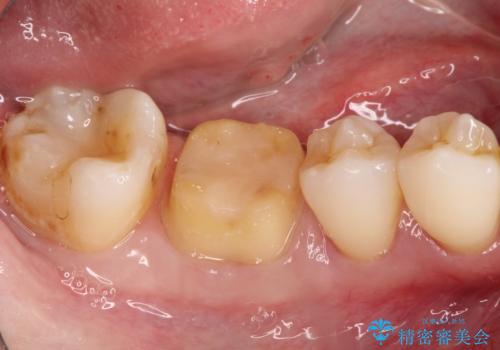

- 以前治療した右下の奥歯の歯の中が虫歯になっている気がするとのことで来院されました。

レントゲン上と視診上では確認できなかったのですが、患者様の希望もあり、一度かぶせ物を外して内部を確認し、オールセラミックを再度装着する計画としました。

やはり内部では少量の虫歯がありましたので、拡大鏡使用して虫歯を除去しました。